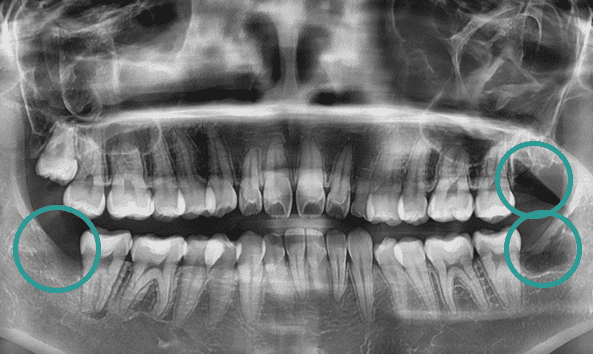

골치 아픈 사랑니, 대학병원 가지 않으셔도 됩니다.

사랑니는 기형적으로 맹출되거나

잇몸 속에 매복되는 경우가 많아 발치가 까다로울 수 있습니다.

특히, 인접 치아를 손상시키지 않고 신경을 보호하며 발치하려면

전문적인 노하우가 필수입니다. 그래서 사랑니 발치는 많은 고민과 망설임을 동반하는

어려운 선택이 될 수 있습니다. 올디플란트치과는 이런 걱정을 덜어드릴 자신이 있습니다.

사랑니 발치를 위해 치과를 찾아 헤매고 계신가요?

매복 사랑니는 신경과 가까워 발치 시

신경 손상의 위험이 높아

일부 동네 치과에서는 치료를 권하지 않기도 합니다.

하지만 올디플란트치과는

대학병원 가기 전에 방문하는 치과로 유명하며,

타원에서 발치하지 못한 케이스도

책임지고 해결해드리고 있습니다.